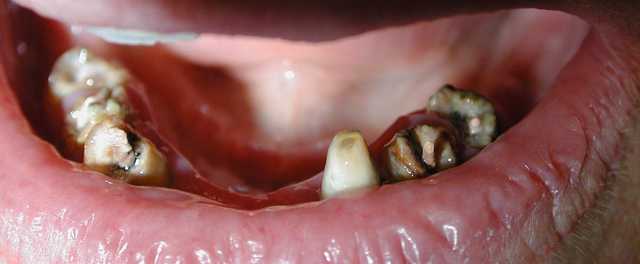

Comme par hasard, ce matin, une patiente (pano jointe) est venue me voir en urgence suite au descellement de sa 34.

(bien sûre les conditions occlusales y sont pour beaucoup : occlusion en bout à bout, édentements postérieurs importants)

Dans la couronne, je constate qu'il reste une partie de dent cassée, du composite et un peu de gutta...

Quel joyeux mélange, pour se donner bonne conscience? ou est-ce là le témoignage d'une profonde méconnaissance de l'intérêt de mettre un tenon lors de la réalisation d'une RCR?